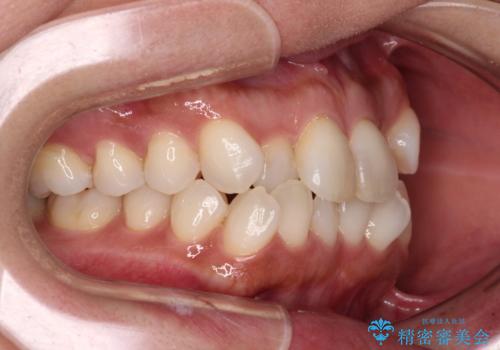

前歯のクロスバイト インビザラインによる矯正治療

- 上下のクロスバイトと前歯のデコボコを気にして来院された患者様です。

インビザラインを用い、IPR(歯と歯の間を削る)と歯列全体を拡大させることで、歯並びを整えていくこととしました。